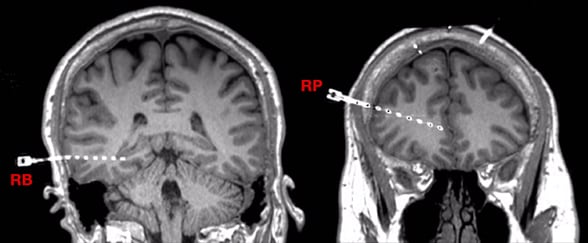

Electrodes placed deep in the brain

Electrodes placed deep in the brain

Imaging shows the placement of electrodes in the right posterior temporal lobe (RB) and right far anterior cingulate (RP).